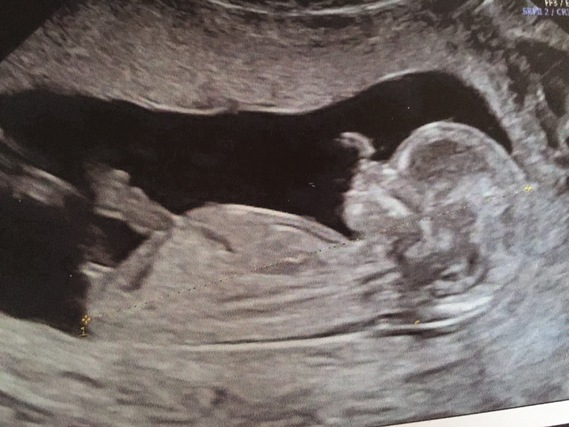

Laurence a fait ce qu’on appelle un déni de grossesse.

Ce n’est qu’à 7 mois et demi qu’elle a découvert qu’elle était enceinte.

Elle avait pourtant fait une échographie et un test de grossesse.

Mais rien n’indiquait qu’elle portait la vie, bien au contraire !.